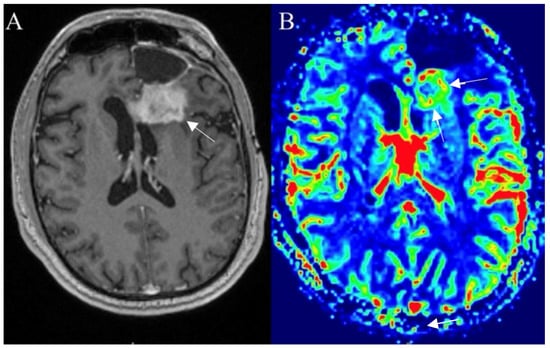

3.6.3. Pseudoresponse

3.6.4. Radiation Necrosis